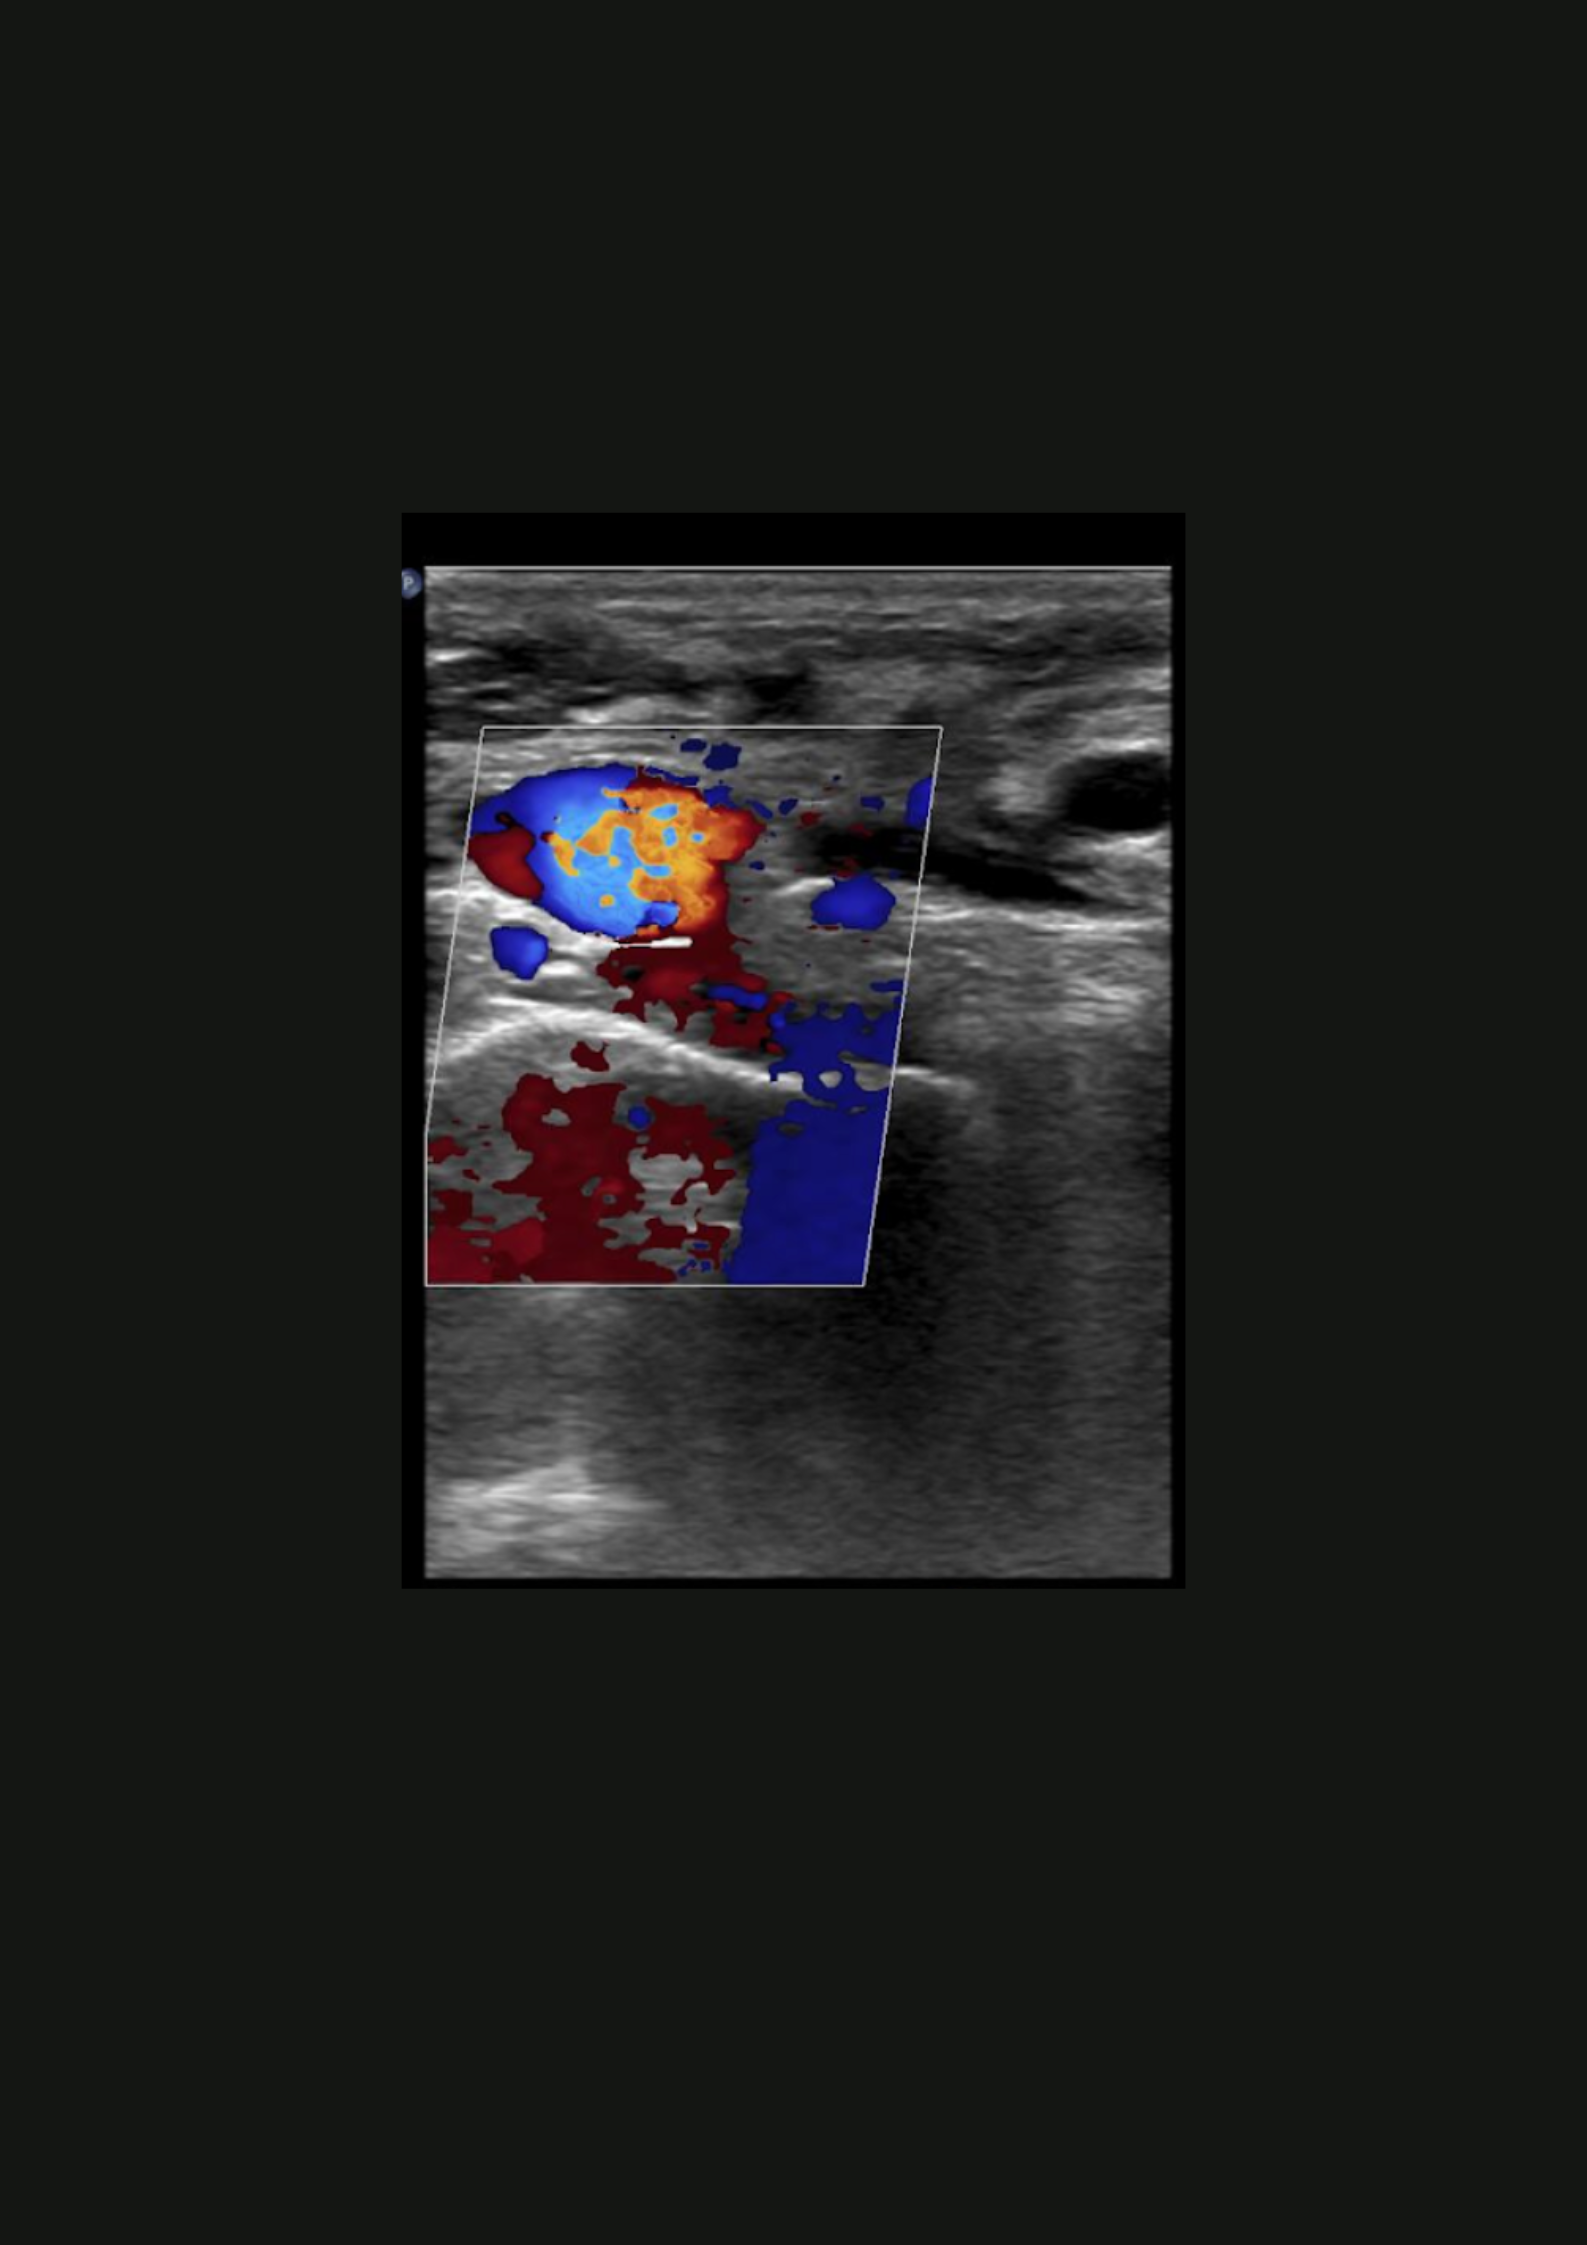

Ante la sospecha de patología muscular sin antecedente traumático, se realiza ecografía.

En la ecografía no apreciamos alteraciones musculares pero observamos dificultad para la compresión de la vena subclavia derecha en extensión.

Trombosis venosa profunda de sublcaiva, innominada, cefálica y yugular derecha.

Se remite a Urgencias del hospital de referencia con hallazgos de coagulación: INR 1.05, fibrinógeno 464, Dímero D 1222; y una ecografía de partes blandas que muestra una trombosis venosa de la vena subclavia derecha y vena innominada, con ligera extensión a la vena yugular derecha y cefálica derecha. Posteriormente, se inicia heparina subcutánea y se realiza fibrinolisis con perfusión de urokinasa. En el estudio de coagulación posterior se determinó una hiperhomocisteinemia y probable síndrome antifosfolípido (Paget-Schroetter).

La enfermedad tromboembólica venosa (ETEV) en extremidades superiores es una entidad poco frecuente. Un tipo de ETEV primaria sería el síndrome de Paget-Schroetter, el cual suele asociarse a ejercicios intensos o bien ser la primera manifestación de un estado trombofílico desconocido hasta ese momento, como en el caso que nos ocupa. La ecografía clínica nos permite un abordaje rápido y sencillo de la patología venosa.